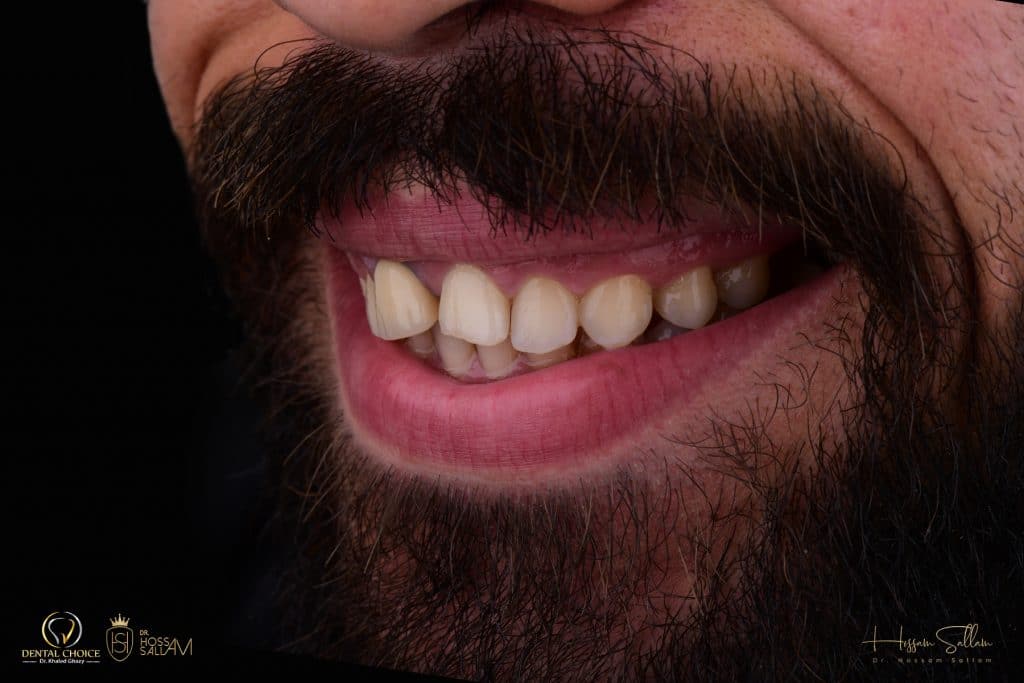

pre operative situation

This pic showing

- Reverse Smile line

- black shadow at buccal corridor region

- in accurate teeth ratio

- gum Smile specially at posterior region

- inadequate zenith position

smile left